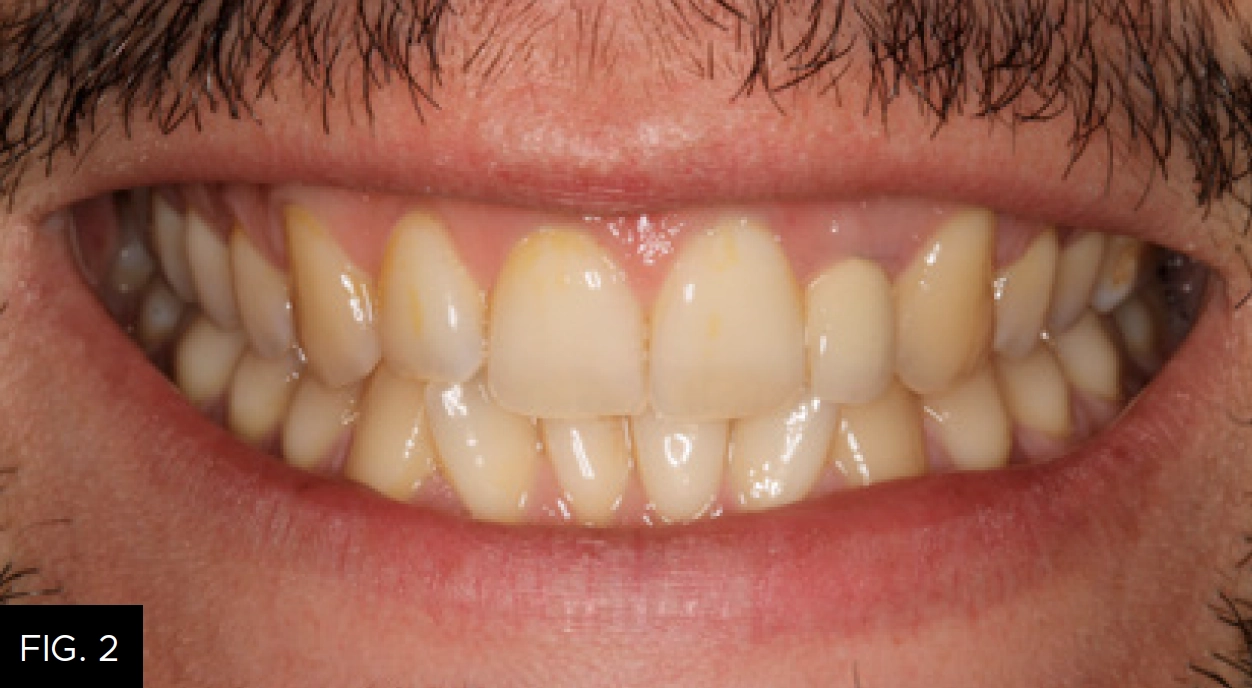

A 30-year-old male presented with a chief complaint that several teeth were sensitive to cold. He also wanted information on how to correct the crowding of his lower teeth and whiten his smile. He had not been to a dentist for at least five years and thought he had never had a dental cleaning. The patient had experienced a traumatic dental injury many years earlier and had been treated with an endodontic post and crown on tooth #10. (FIG. 1-2)

A thorough hard and soft tissue examination was performed, including radiographs and clinical photographs. Periodontally, the patient presented with Class III calculus, several areas of recession, and a thin area of attached gingiva associated with the mandibular bicuspids and canines. In addition, periodontal bone loss was observed radiographically on the distal of tooth #18. A 6-mm clinical probing depth was noted in this area, likely due to an unerupted wisdom tooth. A 4-mm pocket with bone loss associated with #10 also was observed. A root fracture linked to a defective post and crown restoration on that tooth was suspected, as the pocket was clearly observed in one specific area. Several posterior interproximal carious lesions, including one of considerable size on #18, were identified, and treatment with composite restorations was recommended to the patient. An anatomical defect was present on the distal aspect of tooth #7. The patient had Class I occlusion with lower anterior crowding with working interferences present on teeth #4 and #5. The temporomandibular joints appeared healthy and asymptomatic. Apart from the dental issues, the patient was in excellent general health.